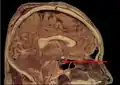

Гипофиз на сагиттальном и корональном срезах МРТ с контрастным усилением